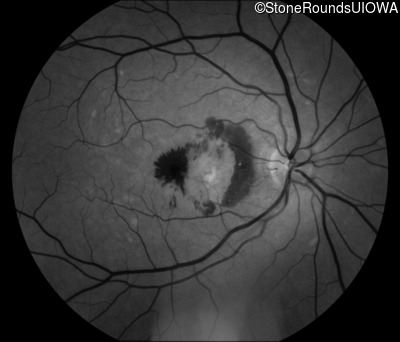

Fundus Photography - Right - 20/250

Exemplar

Fundus Photography - Left - 20/20